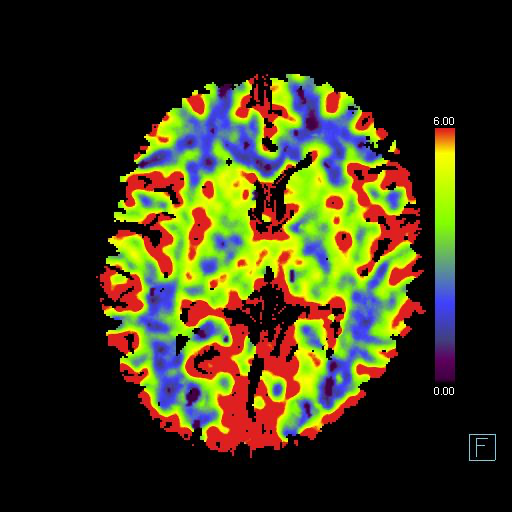

MRI

当院では、患者さんの身体的負担を最小限に抑えつつ、病気の早期発見と正確な診断を可能にする**MRI(Magnetic Resonance Imaging:磁気共鳴画像診断装置)**を導入しています。MRIは、強力な磁石と電波を利用して体内の様子を画像化する検査装置で、放射線を使用しないため、X線被ばくの心配がありません。

またディープラーニングを用いた再構成技術「Deep Resolve」も搭載しており撮像時間を短縮しつつ高解像度の画像を提供しております。更に造影剤を使用せずに脳血流を画像化する技術ASL(Arterial Spin Labeling)も搭載しております。